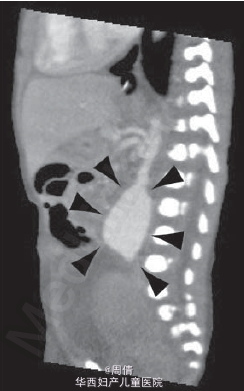

1,2.超声提示在大动脉分叉点以上的降主动脉上有一个动脉瘤,最大直径2cm 3,可见扩大的左脑室和变薄的左侧大脑实质 4,30周时胎儿MRI提示颅腔内的左侧脑室有一个增大的囊性结构

诊断为先天性腹主动脉瘤合并脑穿孔 继续妊娠,孕40周时孕妇产下一个2770g的男婴 体检提示婴儿腹部有一直径2cm的肿块 腹部CT提示降主动脉处有一直径2cm的动脉瘤 脑部CT提示左侧脑室有一囊性结构 出生第三天,MR血管造影提示胎儿期的左颈内动脉阻塞 婴儿6个月时复查腹部CT,提示降主动脉动脉瘤无明显增大,左肾动脉狭窄 因为移植如此小的血管困难太大,所以并未进行手术治疗 但是使用了VP分流器来阻止脑积水的进展